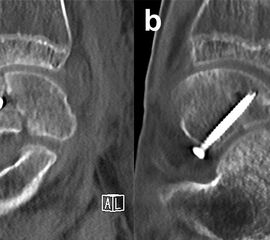

Eine exakte Abgrenzung von Taluskorpus- und Talushalsfrakturen ist allein anhand von Standard-Röntgenaufnahmen nicht sicher möglich. Inokuchi und Mitarbeiter definierten daher Talushalsfrakturen mittels CT, wobei die Frakturlinie distal vor dem Proc. fibularis talis ausläuft 6 (Abb. 1). Es ist anzunehmen, dass sich mit dieser Definition die oben angegebenen Zahlen von den Talushalsfrakturen etwas zu den Taluskorpusfrakturen verschieben, zumal diese mehrheitlich anhand von Röntgenaufnahmen erhoben wurden.

Prinzipiell werden konventionelle Röntgenaufnahmen vom OSG in 2 Ebenen (a.p. in 20° Innenrotation, „Mortise View“, und lateral) angefertigt (Abb. 1a, b). Zusätzlich können spezielle Projektionen wie die Canale oder Brodén-Aufnahme hilfreich sein, wurden in der klinischen Routine aber durch das CT oder DVT weitgehend verdrängt.

Bei in den konventionellen Aufnahmen nicht sicher auszuschließender Talusfraktur bzw. zur genauen Darstellung der Dislokation bei Taluskorpus- oder Talushalsfraktur sollte die Indikation zur CT-Diagnostik großzügig gestellt werden (Abb. 1 c, d). Insbesondere dient die CT-Diagnostik zur genauen Evaluierung der Frakturmorphologie und OP-Planung sowie auch zur Vermeidung möglicher übersehener peripherer Talusfrakturen 4.